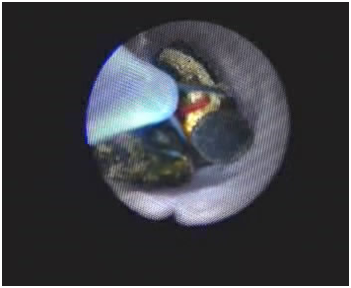

复杂性肝内胆管结石术中胆道镜联合激光碎石术

术中胆道镜取石术